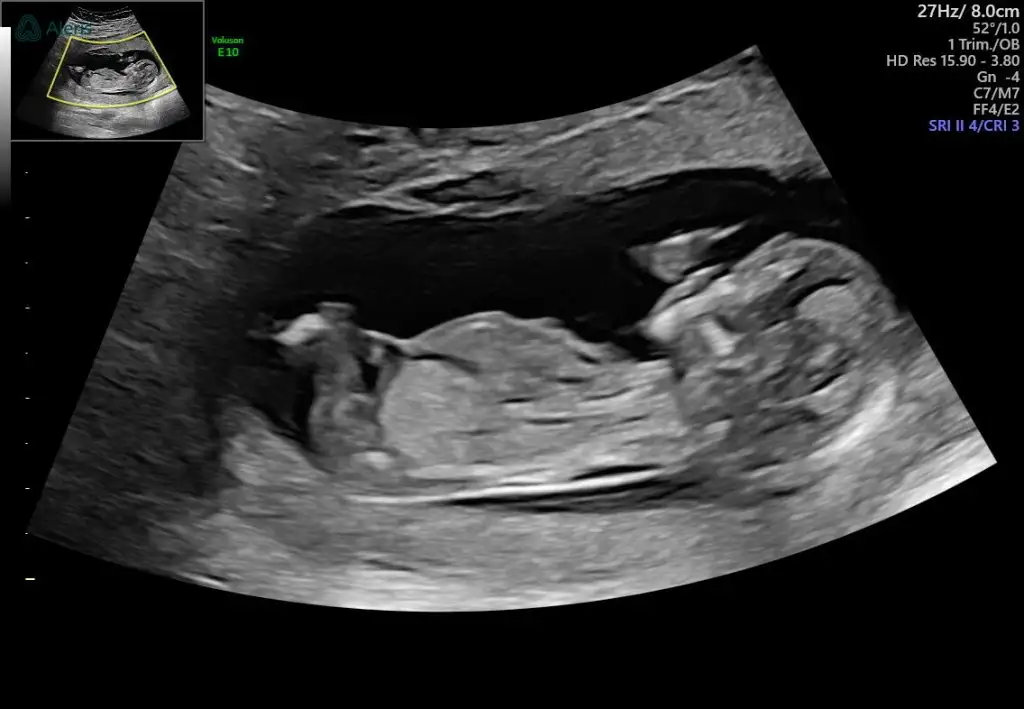

Sizin minik baya utangaçMerhaba kızlar bugün 12+6 olduk bizim minik inatla göstermedi cinsiyetini sonda da iki eliyle bacak arasını kapattı resmen bir sonra ki kontrolüme daha çok var meraktan çatlicam resmen tahminlerinizi alabilir miyim lütfen

Teyzeleri alınıyoruz ama kimse yorum yapmayacak mıAnlayan annelerrrrr biz de çok merak ediyoruz 12+2 sizce cinsiyeti ne ?

Eki Görüntüle 3450798